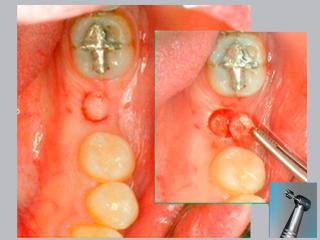

En este sentido nuestro consultorio desarrolla desde 1999 la técnica flapless prescindiendo del bisturí convencional y sin sutura, a través de una incisión circular de 5 mm de diámetro que garantiza un postoperatorio que pasa inadvertido y logra excelente resultado estético.

La técnica quirúrgica flapless (sin solapa) posee varias ventajas comparada con los procedimientos quirúrgicos convencionales, que incluyen la apertura de una solapa (flap) antes de la inserción del implante.